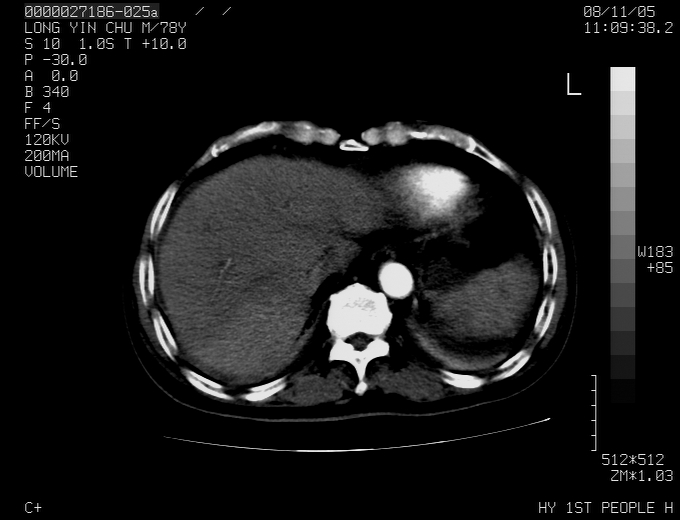

标题: CT16532:M78Y,肝脏病变,请会诊

腹胀,腹痛就诊,男性,78岁,外院b超未见异常。

肝ca,脾肾转移

考虑弥漫性肝癌并脾及双肾转移.双侧胸水.

肝脾肾转移瘤可能性大,左肾不除外梗塞,双侧胸水

考虑弥漫性肝癌并脾及双肾转移,双侧胸水。